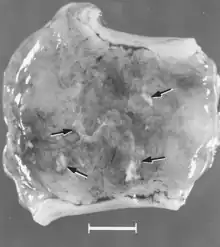

There are numerous macroscopic changes in fetuses infected before they become immunocompetent (Fig. 6). These include a variable degree of stunting and sometimes an obvious loss of condition before other external changes are apparent; occasionally, an increased prominence of blood vessels over the surface of the fetus due to congestion and leakage of blood into contiguous tissues; congestion, edema, and hemorrhage with accumulation of serosanguineous fluids in body cavities; hemorrhagic discoloration becoming progressively darker after death; and dehydration (mummification). Many of these changes also apply to the placenta. Microscopic lesions consist primarily of extensive cellular necrosis in a wide variety of tissues and organs[95][98] (Fig. 7A). Inflammation[98] and intranuclear inclusions[95] also have been described.

In contrast, macroscopic changes have not been reported for fetuses infected after they become immunocompetent for PPV. Microscopic lesions are primarily endothelial hypertrophy[97] and mononuclear cell infiltrations consistent with an immune response.[97][98] Meningoencephalitis characterized by perivascular cuffing with proliferating adventitial cells, histiocytes, and a few plasma cells was seen in the gray and white matter of the cerebrum and in the leptomeninges of PPV-infected stillborn pigs. These lesions were believed to be pathognomonic for PPV infection.[24] Similar lesions have been observed in PPV-infected, live fetuses collected late in gestation[97][98] (Fig. 7B).